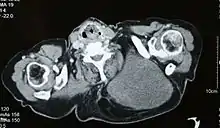

Medical imaging

Ultrasonography may not be able to distinguish a liposarcoma from a benign lipoma, and therefore, MRI is the initial imaging of choice.[4]

MRI of myxoid liposarcoma of high grade, in left axillary region of 40 year old man. Highlighted by the white color. Horizontal section.